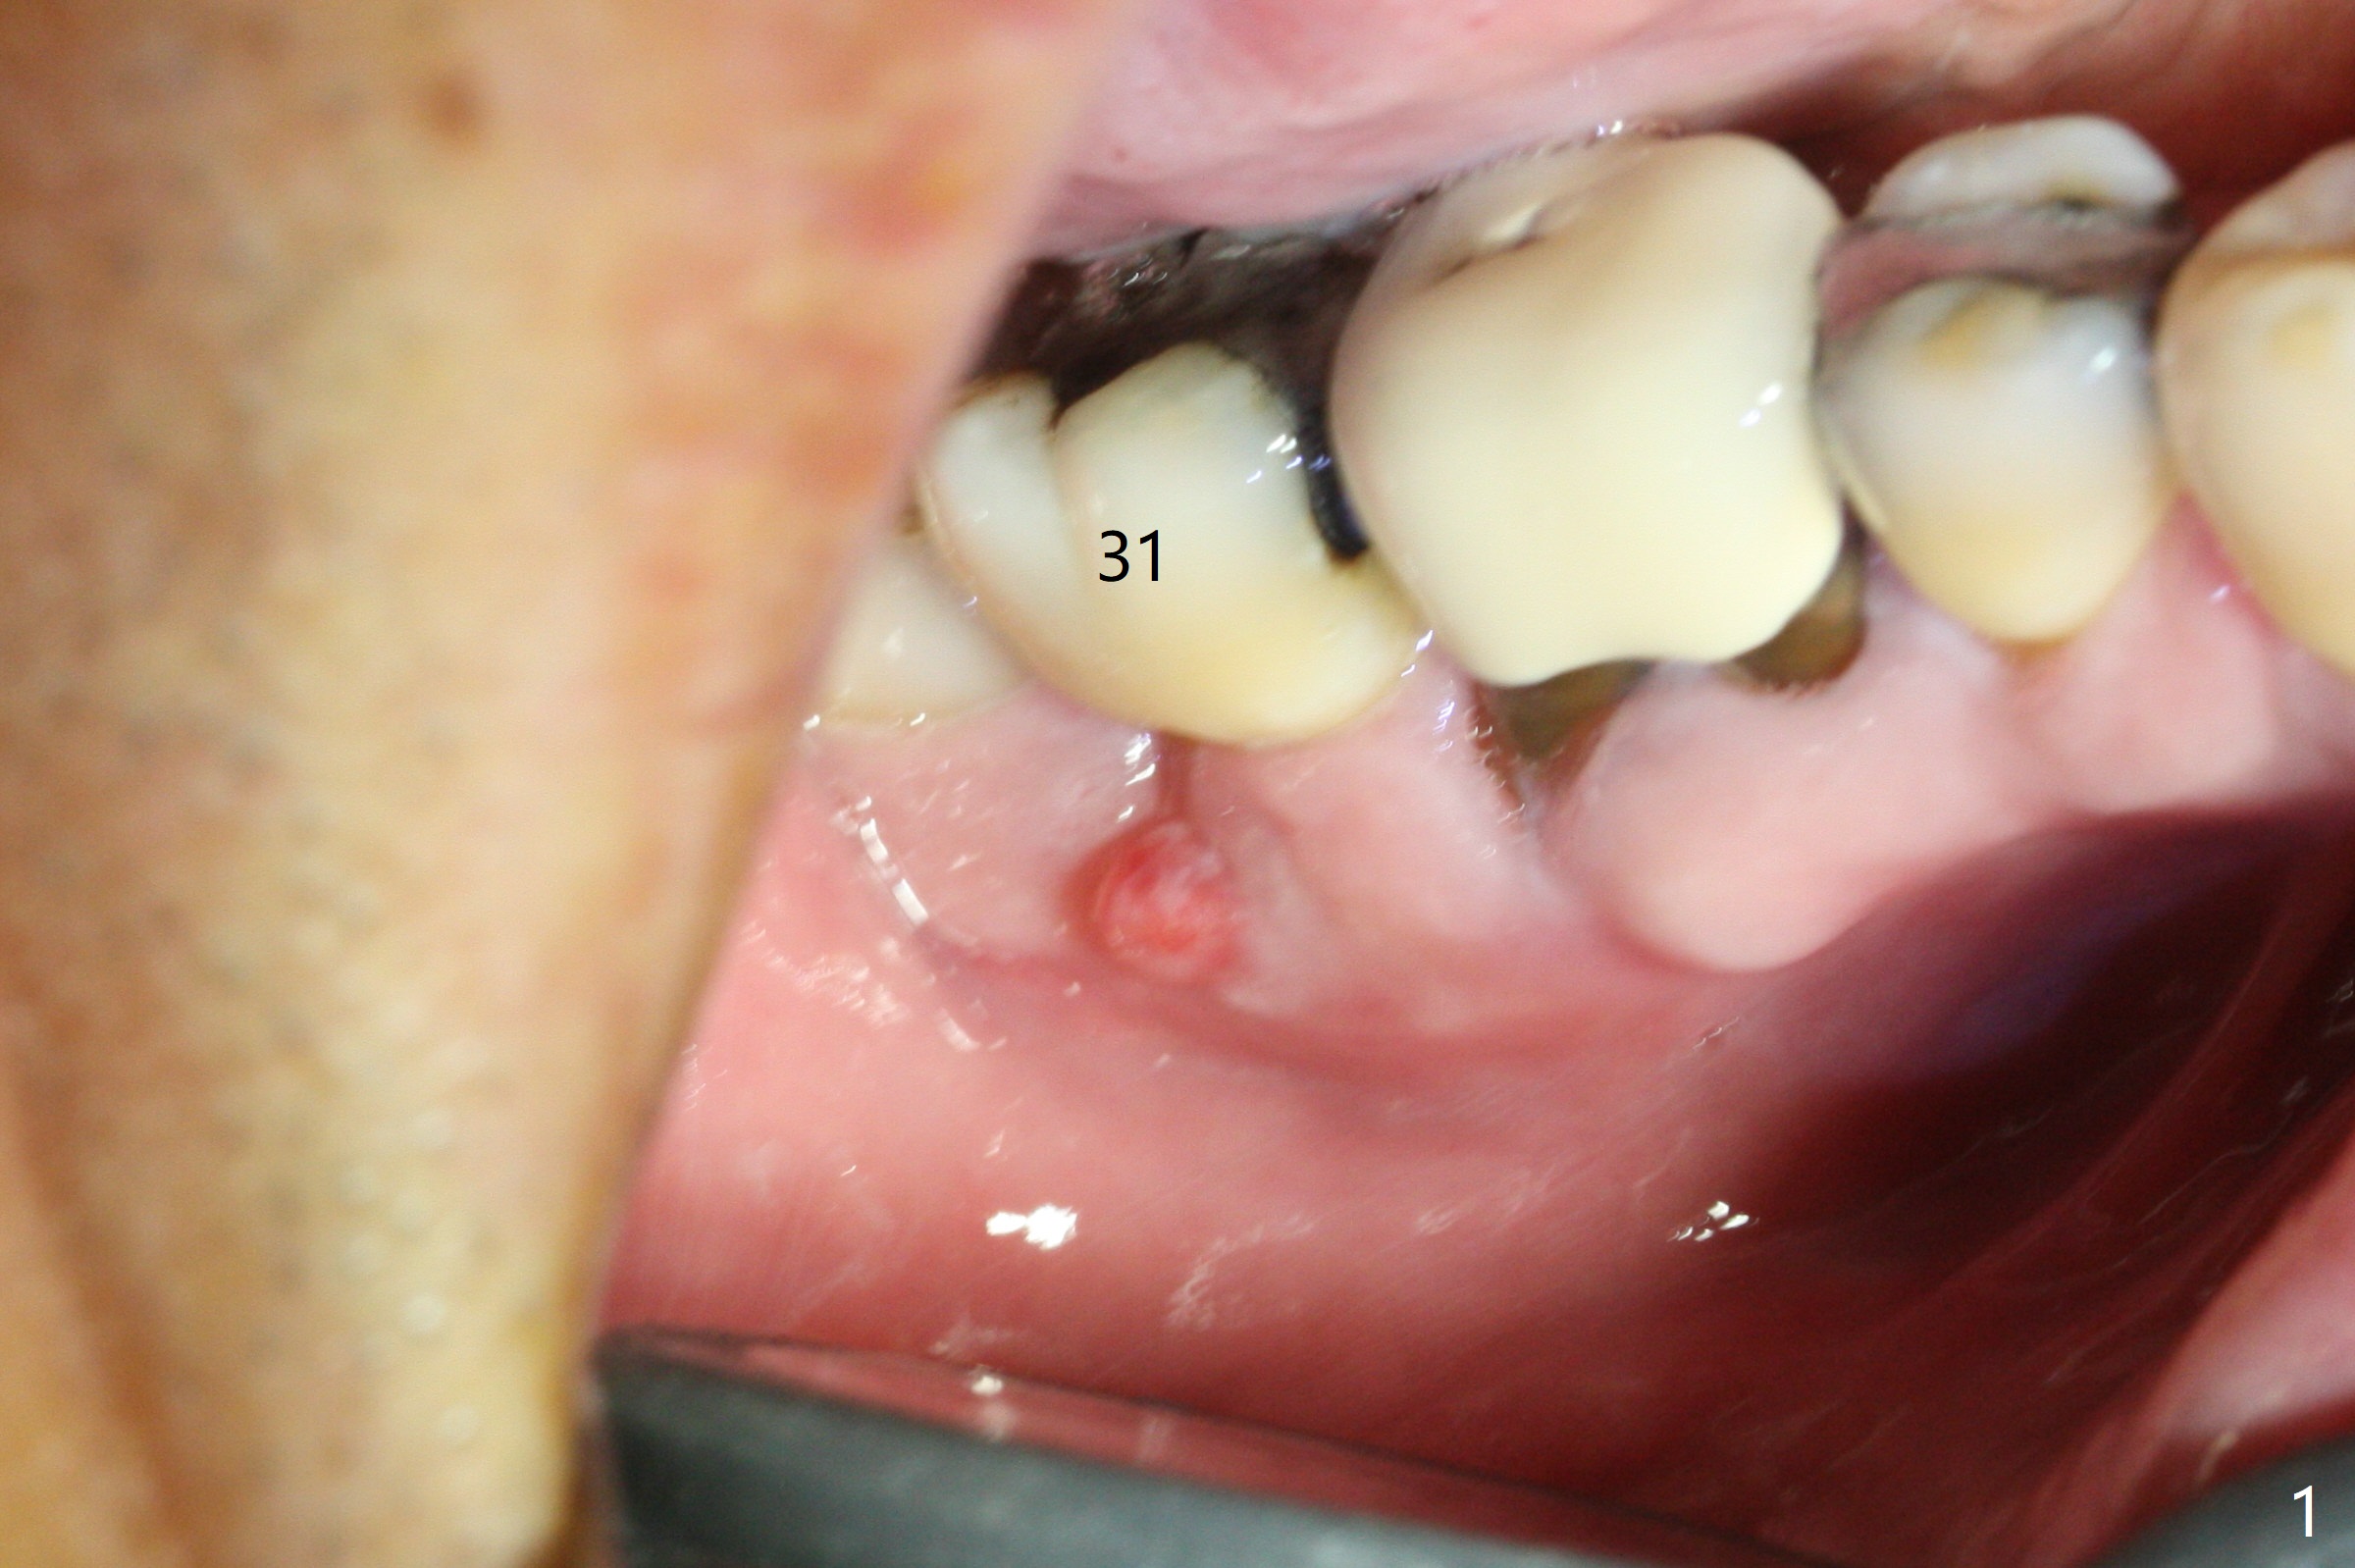

After extraction of the 2nd molar with buccal fistula (Fig.1), osteotomy is initiated beyond the socket for 4 mm (Fig.2,3). Following moving the osteotomy distal and sequential osteotomy, a 4.5x11.5 mm dummy implant is placed equicrestal buccally (Fig.4 ^) with stability; the dummy abutment is 6.5x5(4) mm. A 5x11.5 mm (definitive) implant achieves .>20 Ncm insertion torque (Fig.5). With placement of a 6.5x4(5) mm abutment, Vanilla (Fig.6 *) and Osteogen plug over the graft and in the socket of #32, periodontal dressing is applied. The implant at the 2nd molar placed much deeper than the 1st molar seems to be risky in term of the Inferior Alveolar Canal (Fig.3-6 red dashed line). Several carpules of anesthetics have to be administered in an infiltration manner for pain control. Fortunately there is no postop paresthesia. For an un-compliant patient, socket preservation is a better option. The implant seems to have osteointegrated 4 months postop (Fig.7).